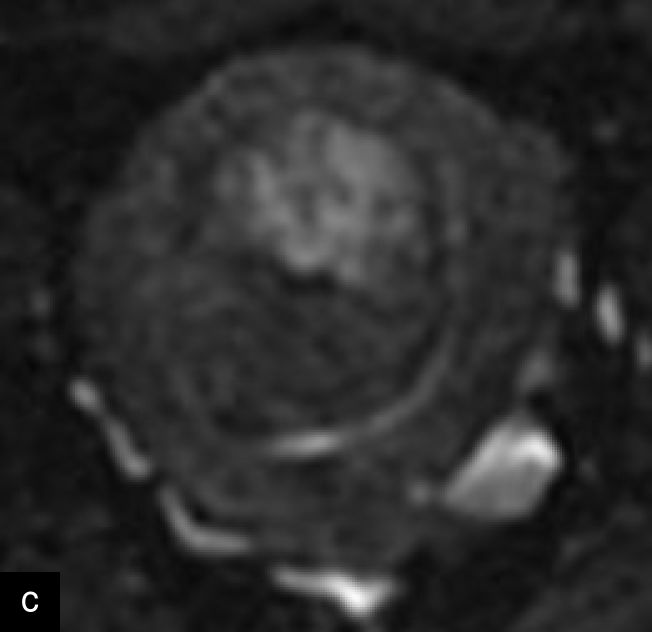

Magnetic resonance imaging (MRI) may help in the preoperative evaluation of uterine masses, when ultrasound findings are inconclusive. MRI offers higher accuracy in soft-tissue contrast, a larger field of view, diffusion imaging and multiplanar capabilities.15 A recent consensus statement has provided a standardized approach to MRI assessment, emphasizing its role in distinguishing uterine sarcomas/STUMP from benign leiomyomas.15 Features suggestive of malignancy include irregular margins; heterogeneous and high signal on T2 weighted imaging; and hemorrhagic and necrotic changes, with central non-enhancement, hyperintensity on diffusion-weighted imaging (DWI), and low values for apparent diffusion coefficient (ADC)15,25,39,40,41 (Figure 7). Diagnostic algorithms have been proposed to support MRI interpretation in differentiating between benign and malignant uterine lesions, and recent studies have explored the use of artificial intelligence to further enhance diagnostic accuracy.42,43,44 Emerging technologies, including radiomics and machine learning, show promise in improving diagnostic precision, although standardization and external validation remain essential.39,45

7

Magnetic resonance imaging (MRI) of a STUMP. (a) Contrast-enhanced MRI showing heterogeneous enhancement of the mass. (b) T2-weighted MRI demonstrating a hyperintense lesion with heterogeneous signal intensity. (c) Diffusion-weighted imaging (DWI) highlighting areas of restricted diffusion. (d) Apparent diffusion coefficient (ADC) map, showing low ADC values suggestive of increased cellularity, aiding in the differentiation of STUMP from benign leiomyomas and malignant leiomyosarcomas.